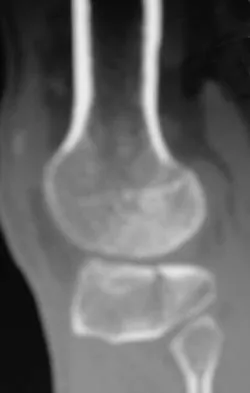

A 5-year-old boy sustained an elbow injury. Examination in the emergency department reveals that he is unable to flex the interphalangeal joint of his thumb and the distal interphalangeal joint of his index finger. The radial pulse is palpable at the wrist, and sensation is normal throughout the hand. Radiographs are shown in Figures 6a and 6b. In addition to reduction and pinning of the fracture, initial treatment should include

Explanation

The findings are consistent with a neurapraxia of the anterior interosseous branch of the median nerve. This is the most common nerve palsy seen with supracondylar humerus fractures, followed closely by radial nerve palsy. Nearly all cases of neurapraxia following supracondylar humerus fractures resolve spontaneously, and therefore, further diagnostic studies and surgery are not indicated. Cramer KE, Green NE, Devito DP: Incidence of anterior interosseous nerve palsy in supracondylar humerus fractures in children. J Pediatr Orthop 1993;13:502-505.